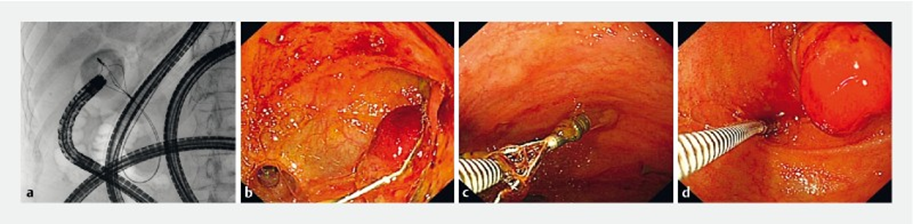

团队完成了一例特殊的ERCP下“网篮嵌顿”患者的内镜下诊治。该患者为57岁女性,20年前因“胆结石”接受了胆囊切除术、胆总管切开探查术和胆肠吻合术治疗,现因怀疑存在胆总管结石、外院取石失败而转诊至我院行ERCP经内镜胆管取石术。术中发现在十二指肠乳头开口处有脓液流出,胆管造影提示胆总管和吻合口处分别存在充盈缺损。胆管插管成功后尝试使用网篮取石(图1)。然而,取石网篮套住充盈缺损后发生嵌顿,反复尝试无法取出。由于插入的网篮无法收回,患者存在被动接受急诊外科手术取出网篮的风险。由于患者曾行胆肠吻合术即消化道改道,团队尝试从改道后另一消化管腔中查看情况。当即换用小肠镜进镜至胆肠吻合口处,见网篮套住部位并非胆管结石,而是一处直径约2 cm的黏膜隆起。随后,在直视下通过活检钳松解,成功取出嵌顿的网篮(图2),并在黏膜隆起处取样本活检,术后病理提示为慢性炎症。

图2 2a.网篮嵌顿后进行小肠镜检查;2b.肠镜画面展示充盈缺损不是胆总管结石,而是吻合口处粘膜隆起;2c、d.异物钳解决网篮嵌顿